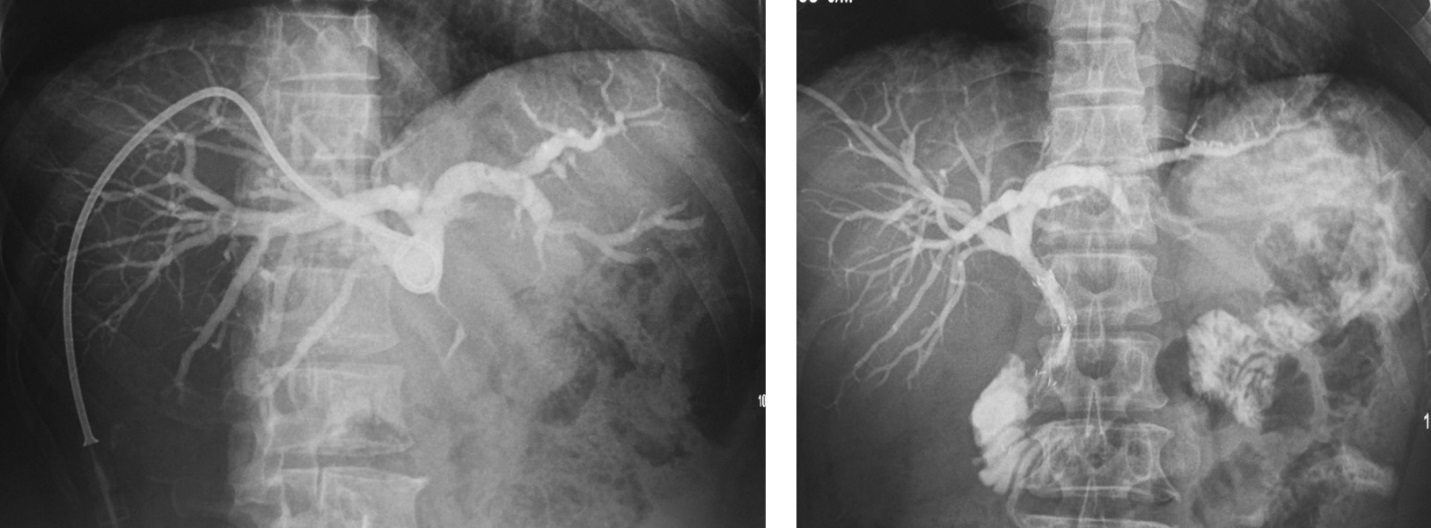

U đường mật rốn gan (Klatskin) xâm lấn hai bên. PTBD giảm áp và đặt stent đường mật qua da hai bên hình chữ Y (Y configuration) tái thông đường mật.